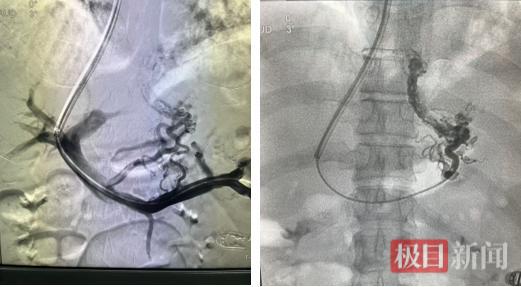

门静脉造影显示,门脉高压、胃冠状静脉迂曲扩张(左图);超选食管胃底静脉造影显示血管扩张明显(右图)

单纯止血、利尿已无法从根本上解除威胁,该院肝病科主任医师徐建良与放射科副主任医师徐庆团队迅速启动多学科会诊,评估后认为,必须从源头上为门静脉这条“高压河流”进行“疏浚降压”。经与家属沟通后,团队决定实施“经颈静脉肝内门体分流术”,即TIPS手术。

月初,高先生经过一系列治疗后生命体征平稳,手术如期进行。在血管造影系统DSA设备引导下,专家们犹如在肝脏内部进行精密的“管道施工”,通过颈静脉这个微小入口,在患者的肝内建立了一条连接门静脉与肝静脉的“分流隧道”,并植入支架。术中造影显示,术后门静脉压力下降,严重曲张的胃底静脉也随之萎缩。术后,高先生的大便颜色恢复正常,精神状态好转,顽固的腹水也得到了控制。